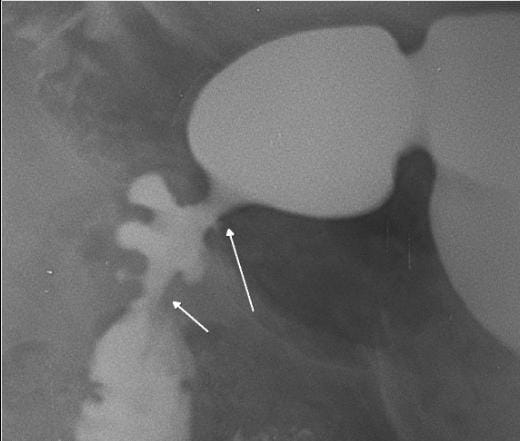

67/Male with symptoms of Gastric outlet obstruction (GOO) distension of stomach, vigurous peristalsis, hold up with stricture of D1- proximal D2

Radiological signs of a deformed duodenal bulb, often caused by chronic scarring from peptic ulcer disease, include a "cloverleaf" appearance (due to multiple pseudodiverticula and spasm), persistent irregularity, and base line tenting. Other signs include ulcer craters, narrowing, and, in severe cases, strictures or "pseudodiverticulum" formation.